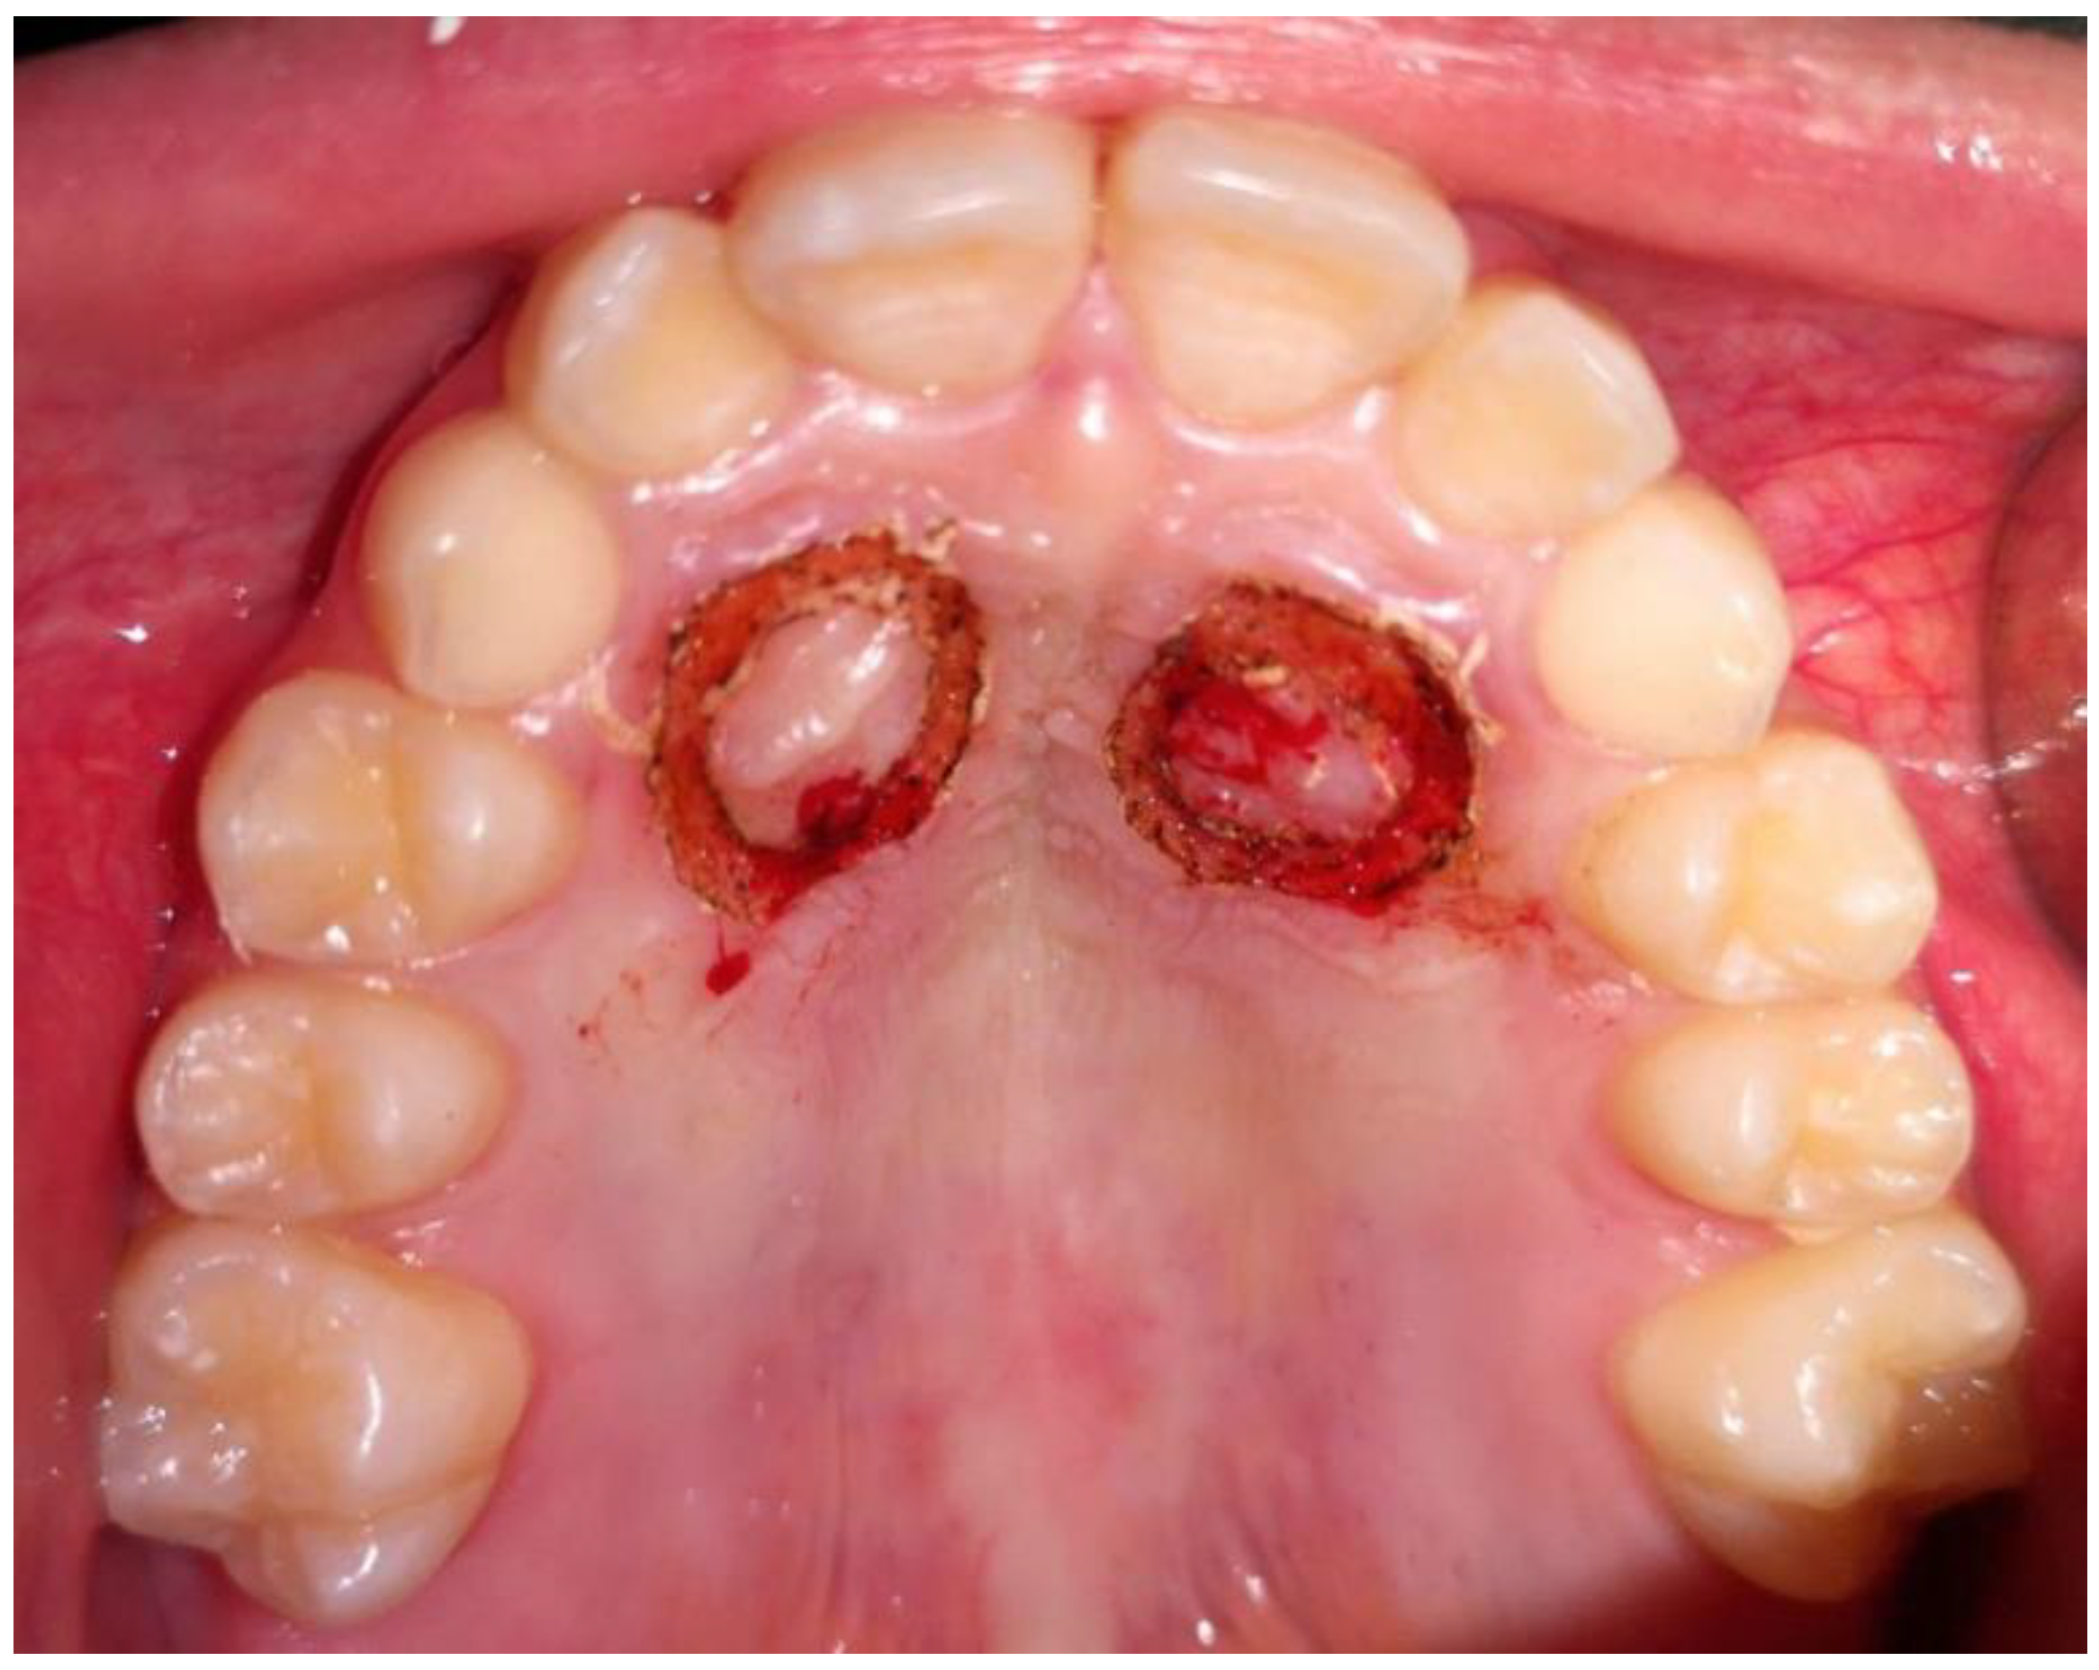

2. Case Presentation